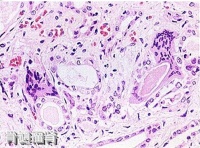

骨髓瘤肾(显微镜下图片)

%~60%。同时尿中草酸钙结晶与碱性磷酸盐增多。

骨髓瘤细胞(低倍镜所见)

镜下可见瘤体主要由大量密集的瘤细胞组成,间质极少。瘤细胞多呈圆形或卵圆形,但具有不同程度的幼稚性。按分化程度的差异,可分为高分化型(小细胞型)及低分化型(大细胞型)两种。前者分化较成熟,体积小,具有圆形而偏心性的核,染色质呈车轮状,亦称浆细胞型骨髓瘤;后者分化差,体积大,有时有双核,核仁明显,核分裂较多见,亦称网状细胞型骨髓瘤。